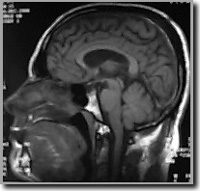

MRI is zonder twijfel een van de betere methode om

neurologische aandoeningen op te sporen, denken we hierbij aan scans

van de hersenen en het ruggenmerg.